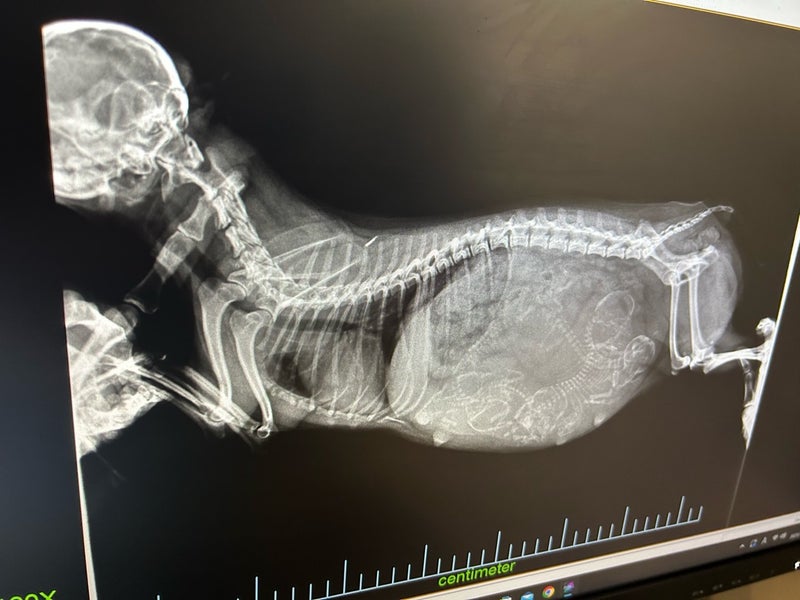

今日は、出産前のレントゲン検査に行ってきました!

お腹の中には4ベビーいるそうです

ここ2〜3日中ではないかと言われています